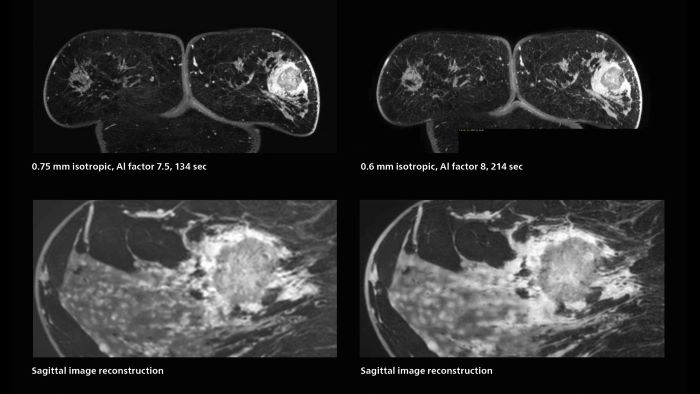

3D MRI of breast cancer

Scanning was performed with two different voxel sizes. AI enabled volume MRI allows image reconstruction in other directions. Biopsy revealed invasive ductal carcinoma in this patient. Performed on Elition X.

Fast AI-enabled MRI of breast cancer: comparing 3D acquisitions with 0.75 mm and 0.6 mm isotropic voxels.

The hospital’s routine ExamCards for breast imaging include:

• ExamCard for 0.7 mm isotropic, 2:09 min, acceleration factor 7.5

• ExamCard for 0.6 mm isotropic, 3:37 min, acceleration factor 8